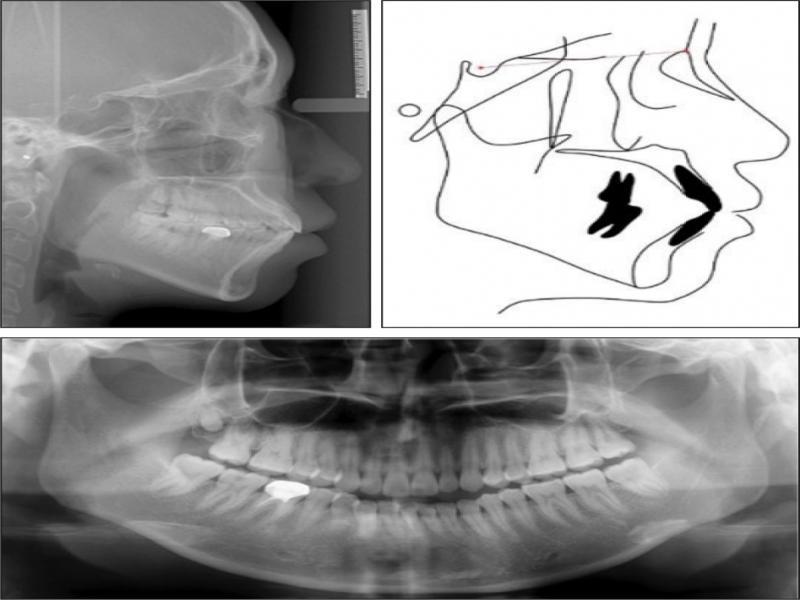

Panoramic radiography showed that the 46 was a crowned tooth with previous root canal treatment. The four third molars were present (Figure 3). A cephalometric analysis indicated a skeletal Class I pattern with an average mandibular plane angle. Both the maxillary and mandibular incisors were proclined (Figure 3).

Pretreatment cephalometric radiograph (top left) and tracing (top right) and panoramic radiograph (bottom).

Option two: Invisalign treatment to distalise both dental arches, retract and retrocline the upper and lower incisors, and to decrease the lip prominence. Miniscrews would be required to reinforce posterior anchorage. Elastics applied between the miniscrews and precision cutouts in the clear aligners would be used to achieve the distalisation of both arches (Figure 4). The third molars 28, 38 and 48 would be extracted; the 18 was not extracted but monitored during treatment because it was affected by microdontia and in a high position with an expected inconsequential impact on the distalisation of the dentition in the respective quadrant. The extraction of the deeply impacted 18 was likely to involve risks of tearing of tissue flaps and the excessive removal to bone and overlying soft tissue (Figure 3).